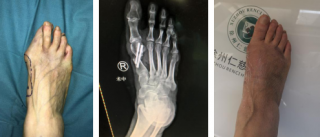

踇外翻俗称“大脚骨”,是一种常见的踇趾向足的外侧过度倾斜、第一跖骨内收的前足畸形,女性居多。

1、严重足部畸形,影响美观

如何治疗踇外翻?

第三代微创踇外翻矫正手术

sararz足踝团队采用4毫米低频超声骨刀微创截骨,切口很小无需缝合;低频超声骨刀锋利、精准、自带注水降温,能更好地保护骨骼血运,使得截骨处更快愈合,手术基本无血渗出,完美修整踇外翻,术后第二天就能下地行走。